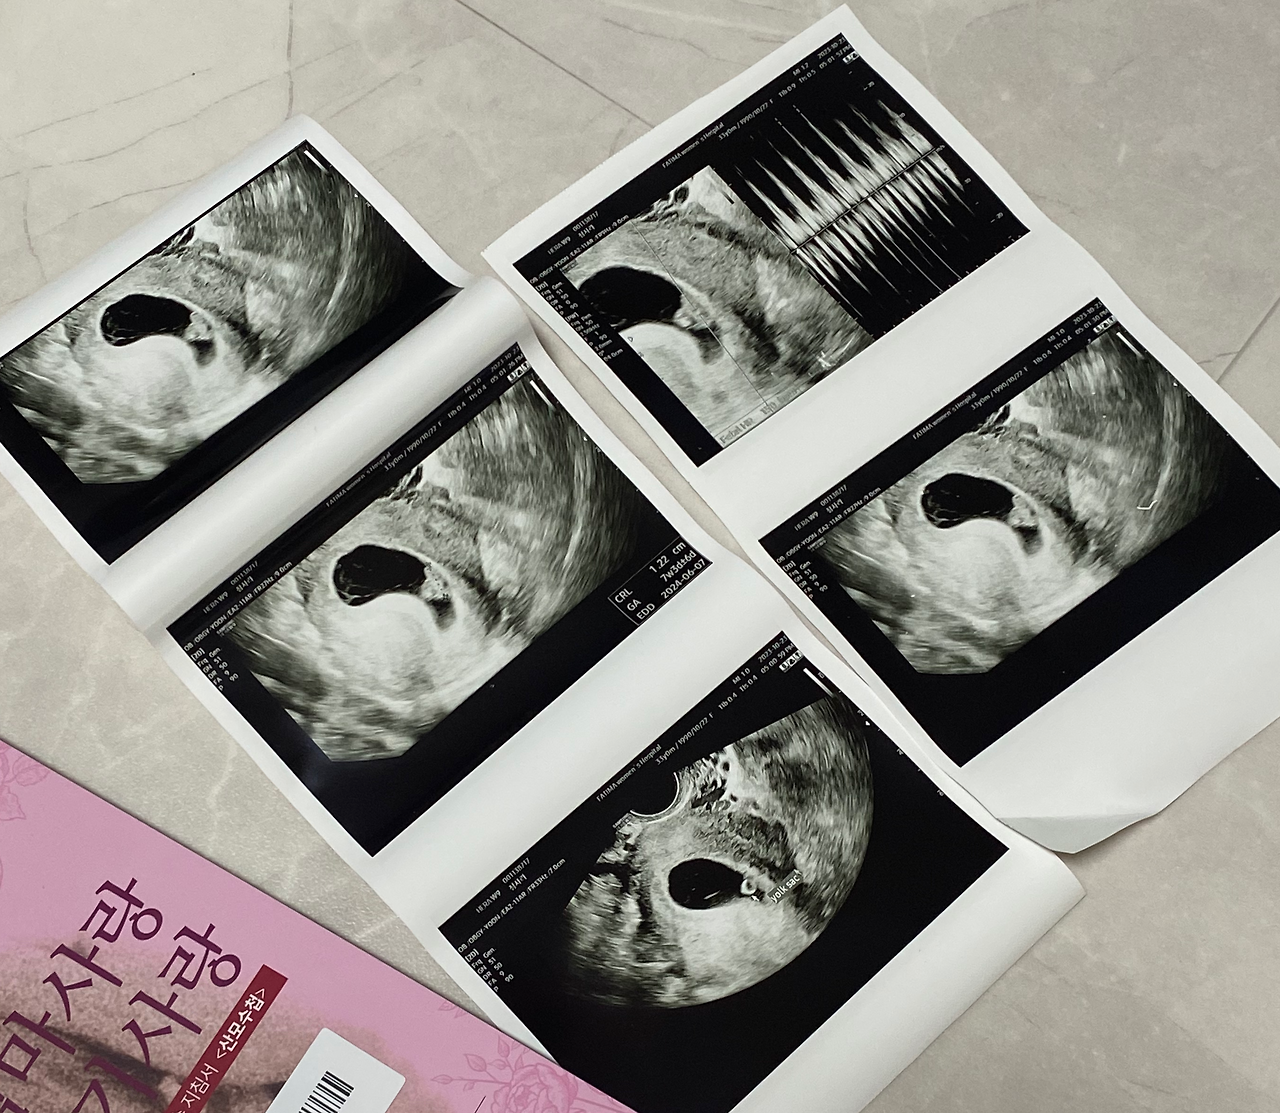

설명을 듣지 않으면 알아보기 어려운 형태의 태아에게 두근두근 뛰는 작은 심장이 보였고, 웅장한 북소리와 같은 심장소리도 함께 들렸다. 보통 첫 심장소리를 들으면 감격의 눈물을 흘린다는데, 남편이 없이 혼자여서 그런 건지 나는 어떤 반응을 해야 할지 몰랐다. 애매하게 감동적인 것 같으면서 '우와..' 밖에 할 말이 없고, 내 뱃속에 이런 생명체가 존재한다는 게 믿기지 않으면서 이상한 기분이 들었다. 그저 주수에 맞게 잘 크고 있고 다른 이상이 없다는 사실에 안도감이 더 들었을 뿐.

태아가 심장이 뛰는 걸 확인하니 병원에서 산모수첩을 주었다. 그리고 초음파 진료 영상을 녹화하여 어플로 다시 확인 할 수 있는 유료서비스까지 신청해서 받았다. 함께 진료를 보지 못한 남편에게도 들려줘야하니까!